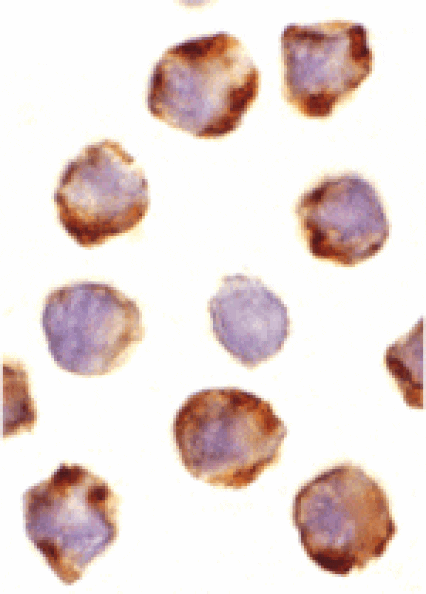

Rabbit polyclonal antibody to PUMA for E, WB, ICC and IF.

E, WB, ICC, IF